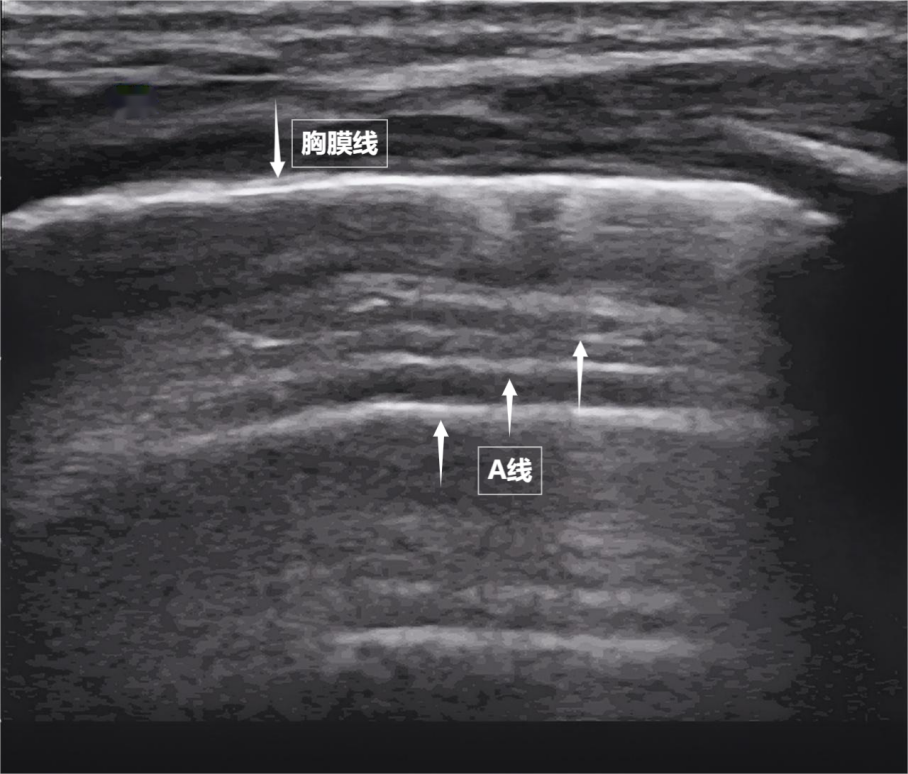

第一景:“海岸线与海浪”——胸膜线与A线

当声波穿过胸壁肋骨缝隙,首先会遇到紧贴肺表面的光滑薄膜——壁层胸膜和脏层胸膜。两者紧密相贴,中间没有多余的气体或液体。它们在屏幕上呈现为一条明亮、光滑的水平线,共同构成了胸膜线。这条线就是肺的“海岸线”。在它的下方,由于肺泡内大量气体对声波的强烈反射,会出现一系列与胸膜线平行的、等间距的、重复出现的明亮平行线,像海浪般不断向屏幕深处延伸,这就是A线(见下图)。A线是正常含气肺部的典型标志。它的存在直接提示肺表面含气充足,胸膜腔内无异常积液或气体。

▲图为正常新生儿肺部超声表现